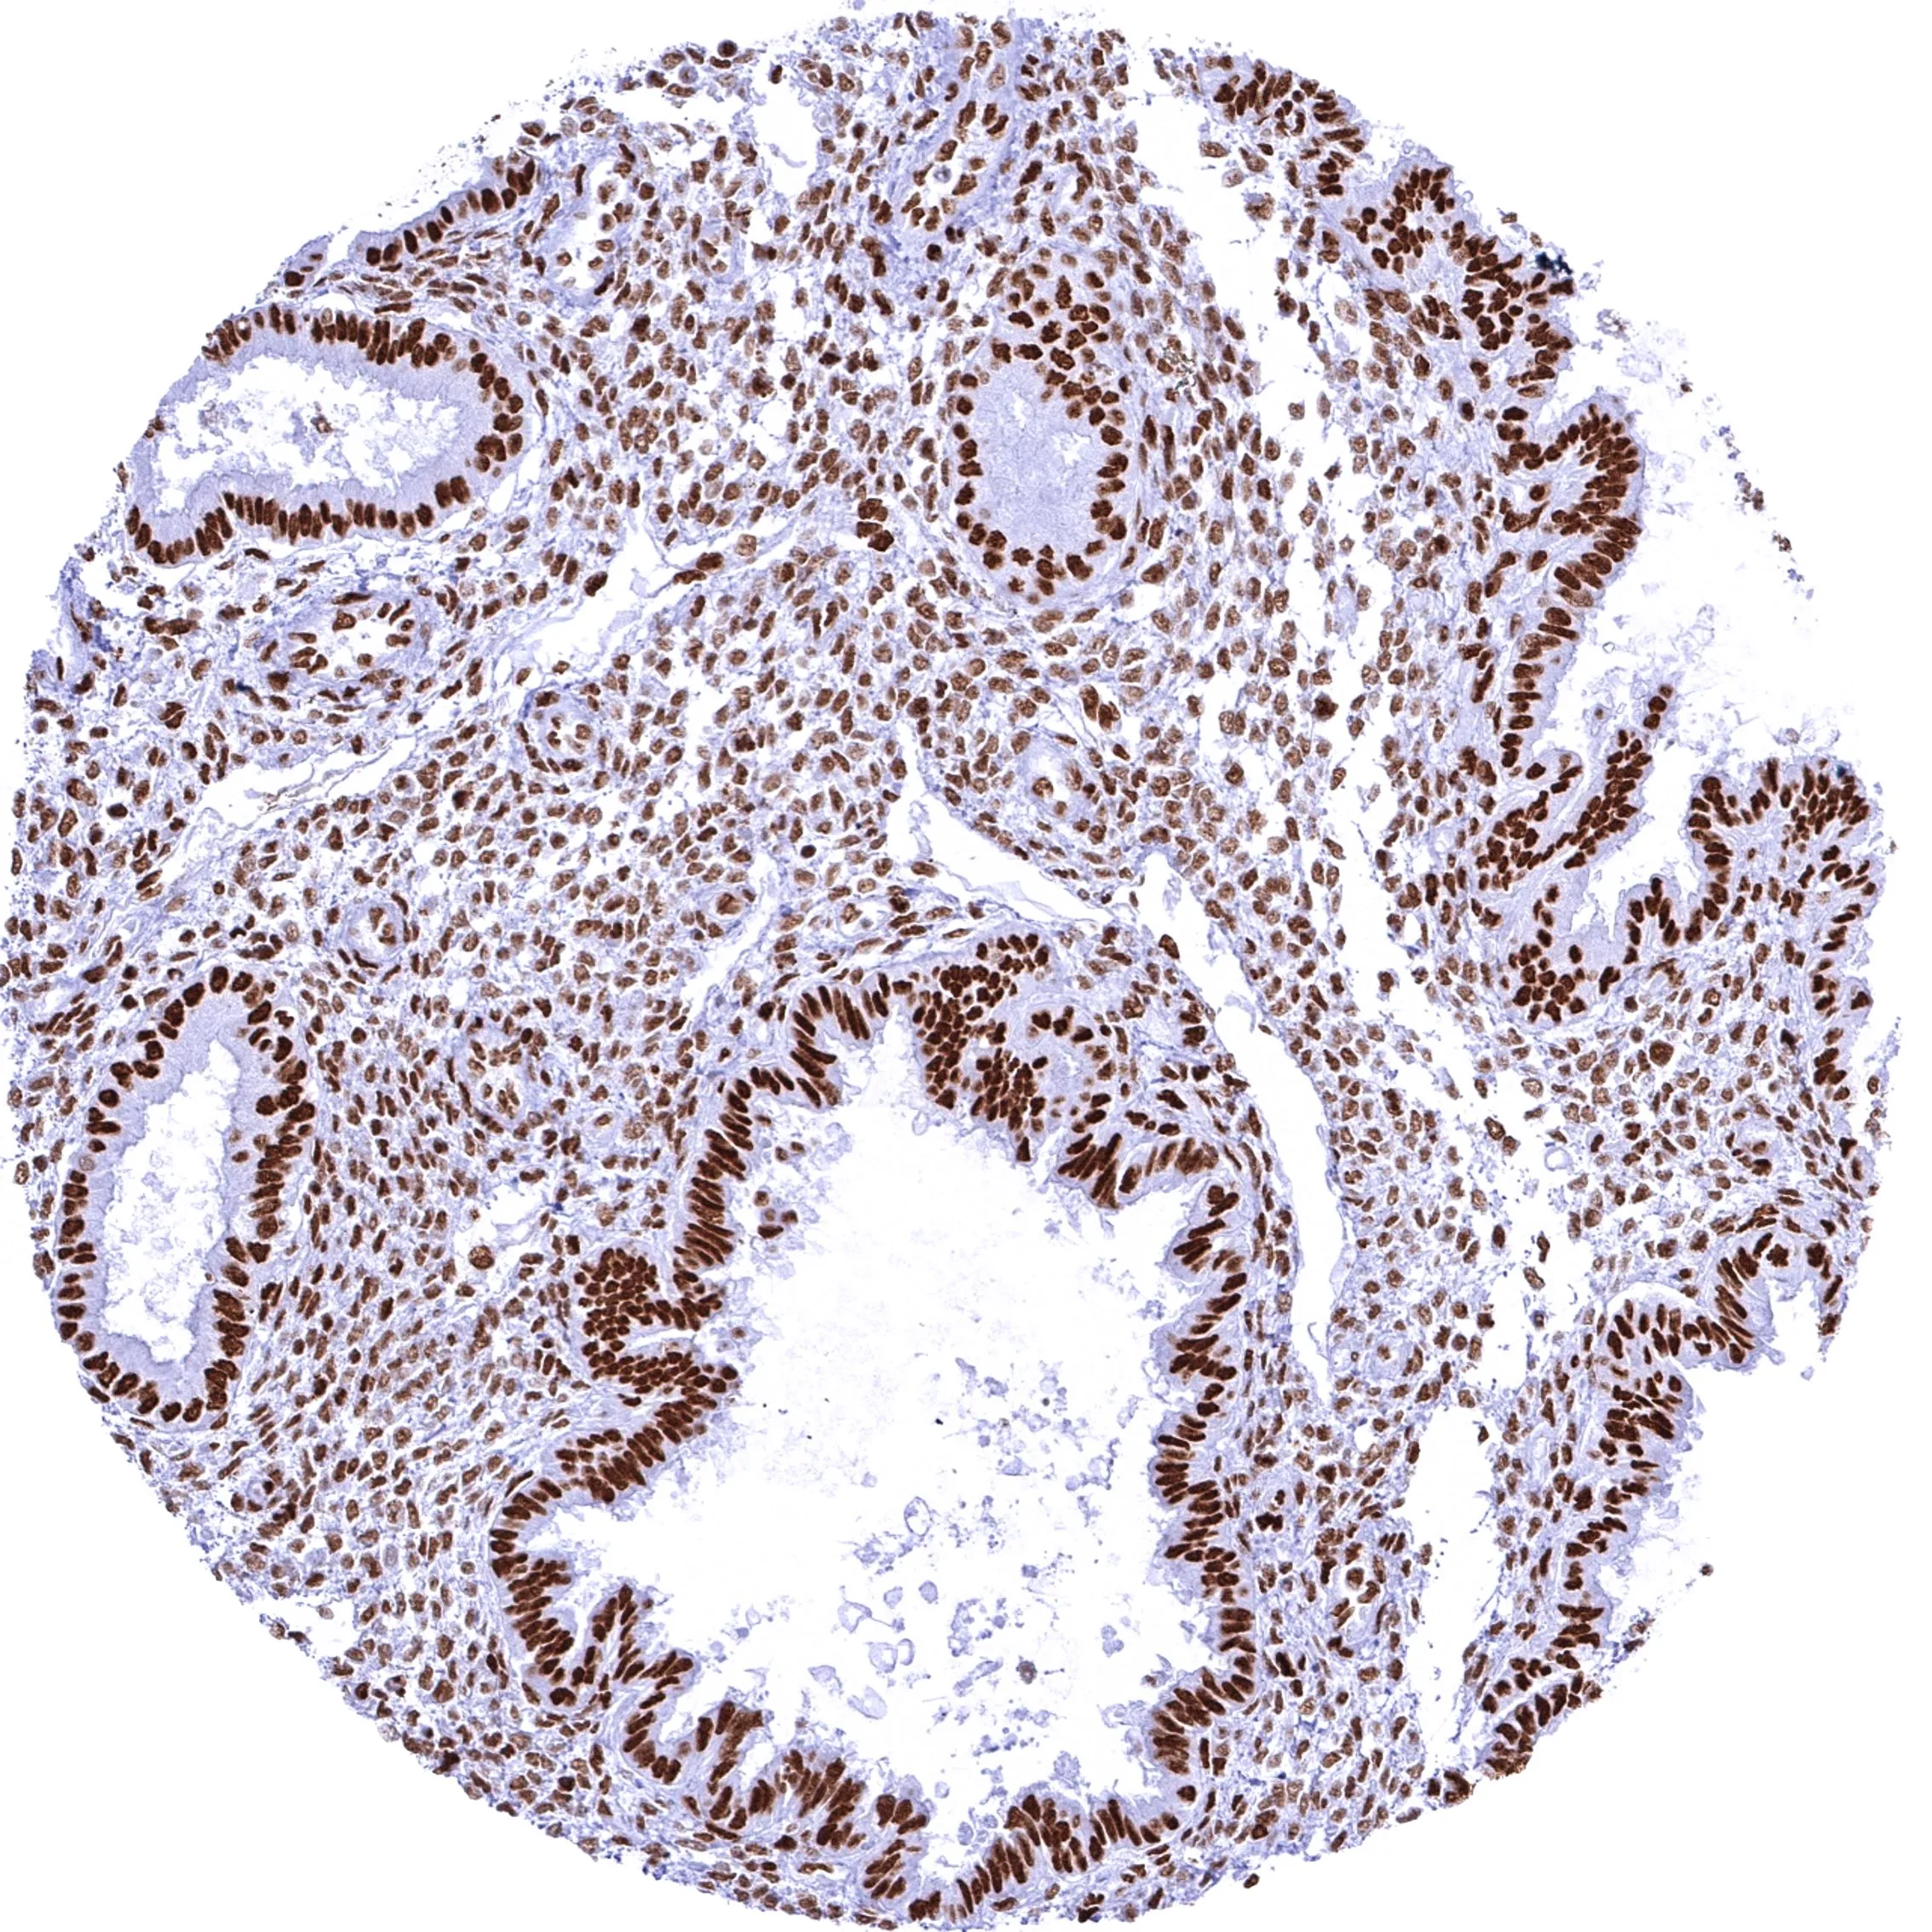

Anti-BRG1 antibody [MSVA-397R] HistoMAX™ used in IHC (Paraffin sections) (IHC-P). GTX04486

GTX04486 IHC-P Image

IHC-P analysis of human endometrium tissue using GTX04486 BRG1 antibody [MSVA-397R] HistoMAX™.

Intense nuclear BRG1 staining of all cell types of the endometrium.